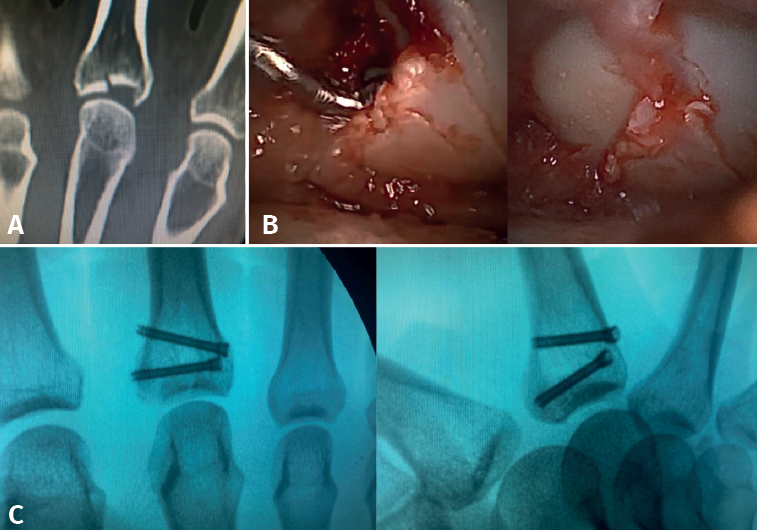

- Fractures with avulsion of the insertion of the collateral ligament (Figures 2 and 3).

Once the fragments have been reduced, 0.8 or 1.0 Kirschner wires are used to maintain reduction (Figure 7). Sometimes we can only maintain reduction by applying a stop, to prevent the osteochondral fragment from collapsing. Depending on the fracture pattern and the surgeon's preference, we can use conventional screws, cannulated screws, etc. (Figures 8 and 9).